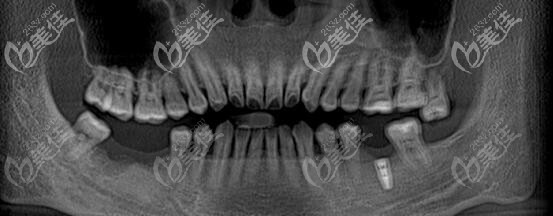

牙齿情况:左下后牙种植过一颗,右下后牙缺失两颗;

治疗方案:顾客咨询后,要求植入诺贝尔种植体;

做手术的时候没感觉多疼,更重要的是手术过程很快,我选诺贝尔种植体的原因之一就是:不用等待拔牙后伤口的愈合,可以做即刻修复,减少了手术的次数,也缩短了治疗时间;直径3.0mm—4.9mm,长度7mm—18mm,植体的种类还是较多的。